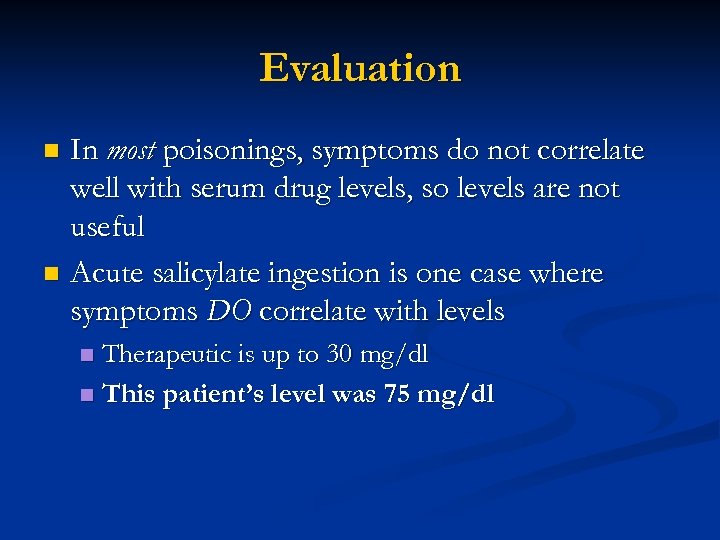

Evaluation In most poisonings, symptoms do not correlate well with serum drug levels, so levels are not useful n Acute salicylate ingestion is one case where symptoms DO correlate with levels n Therapeutic is up to 30 mg/dl n This patient’s level was 75 mg/dl n

Evaluation In most poisonings, symptoms do not correlate well with serum drug levels, so levels are not useful n Acute salicylate ingestion is one case where symptoms DO correlate with levels n Therapeutic is up to 30 mg/dl n This patient’s level was 75 mg/dl n